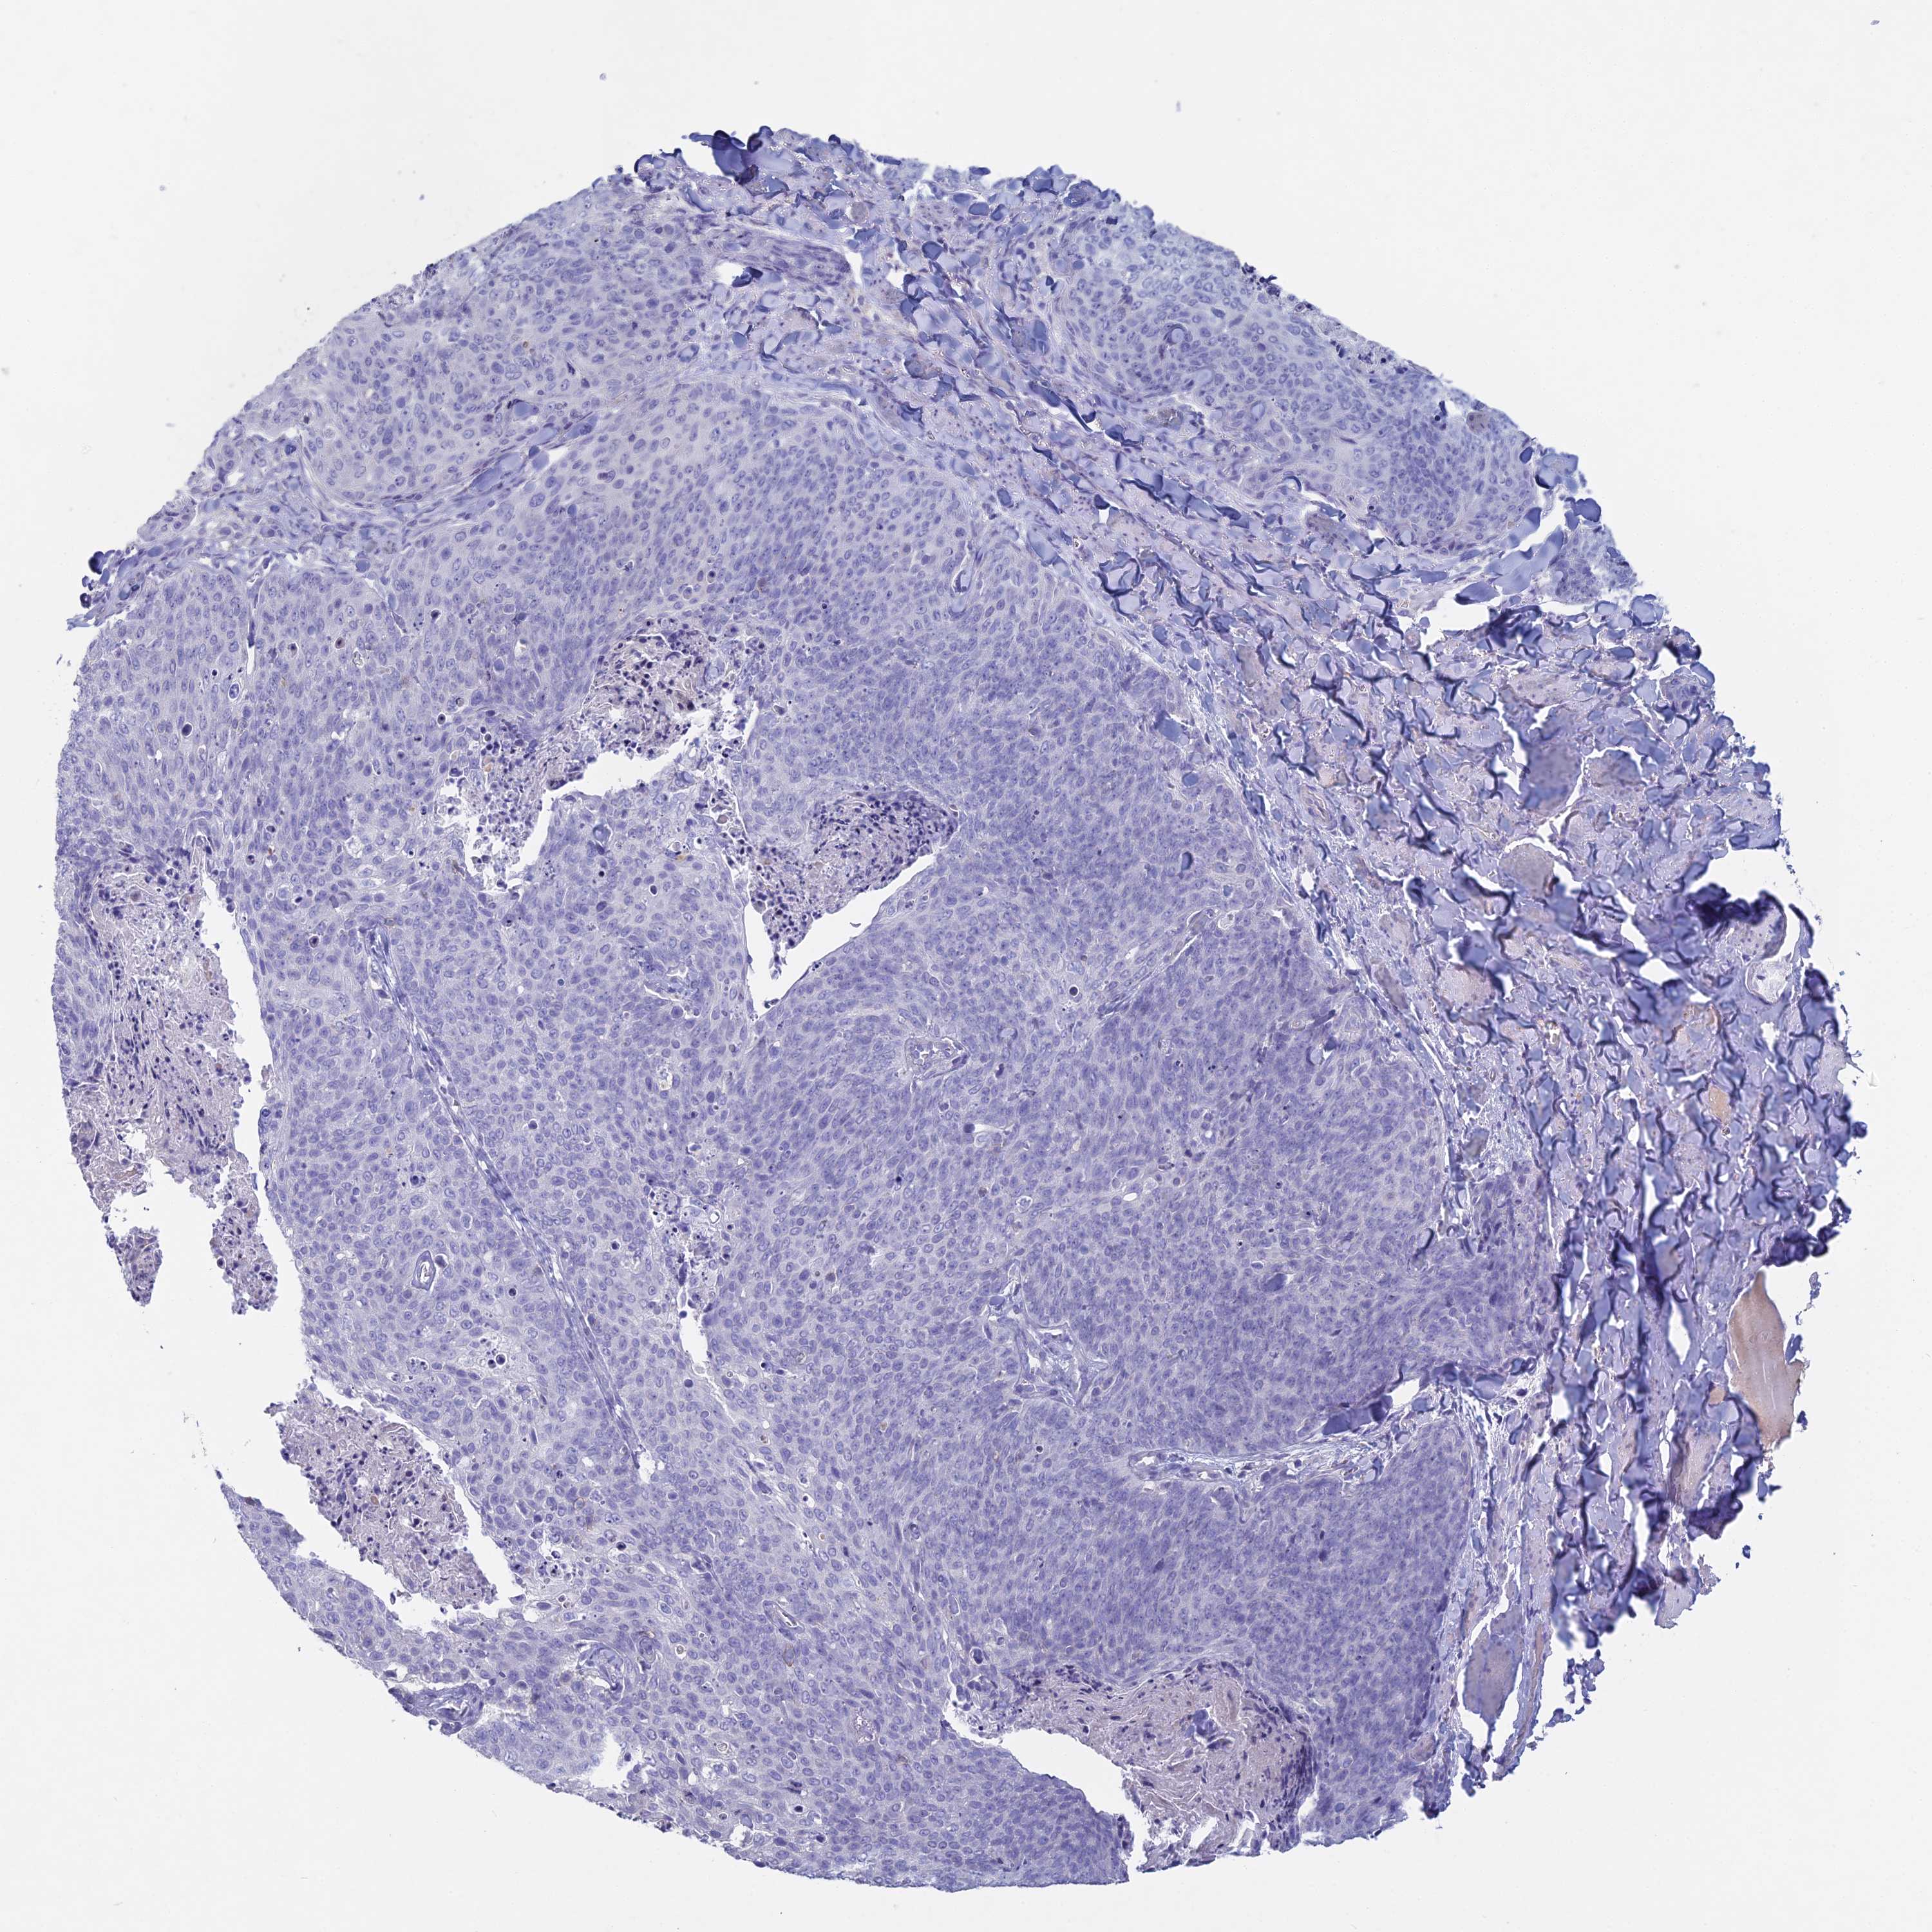

SKIN CANCER - Protein expressioni

A mouse-over function shows sample information and annotation data. Click on an image to view it in a full screen mode. Samples can be filtered based on level of antibody staining by selecting one or several of the following categories: high, medium, low and not detected. The assay and annotation is described here.

Each image is clickable and will lead to virtual microscopy that enables deeper exploration of all samples and also displays staining intensity scores, fraction scores and subcellular localization as well as patient and tissue information for each sample.

Antibody HPA039835

Antibody CAB000142

Antibody CAB018071

Basal cell carcinoma

Squamous cell carcinoma, NOS

Squamous cell carcinoma, metastatic, NOS

Squamous cell carcinoma in situ, NOS

Adnexal tumor, benign